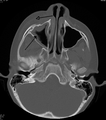

A computed tomograph showing infection of the ethmoid sinus

Maxillary sinusitis caused by a dental infection associated with periorbital cellulitis